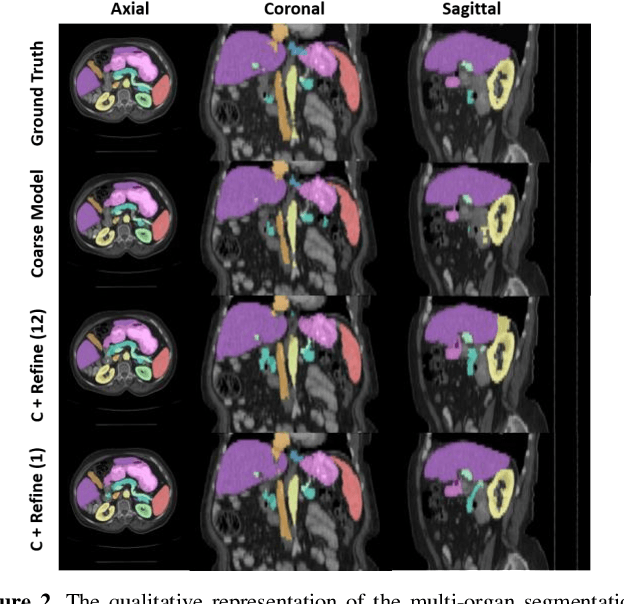

Abstract:Performing coarse-to-fine abdominal multi-organ segmentation facilitates to extract high-resolution segmentation minimizing the lost of spatial contextual information. However, current coarse-to-refine approaches require a significant number of models to perform single organ refine segmentation corresponding to the extracted organ region of interest (ROI). We propose a coarse-to-fine pipeline, which starts from the extraction of the global prior context of multiple organs from 3D volumes using a low-resolution coarse network, followed by a fine phase that uses a single refined model to segment all abdominal organs instead of multiple organ corresponding models. We combine the anatomical prior with corresponding extracted patches to preserve the anatomical locations and boundary information for performing high-resolution segmentation across all organs in a single model. To train and evaluate our method, a clinical research cohort consisting of 100 patient volumes with 13 organs well-annotated is used. We tested our algorithms with 4-fold cross-validation and computed the Dice score for evaluating the segmentation performance of the 13 organs. Our proposed method using single auto-context outperforms the state-of-the-art on 13 models with an average Dice score 84.58% versus 81.69% (p<0.0001).